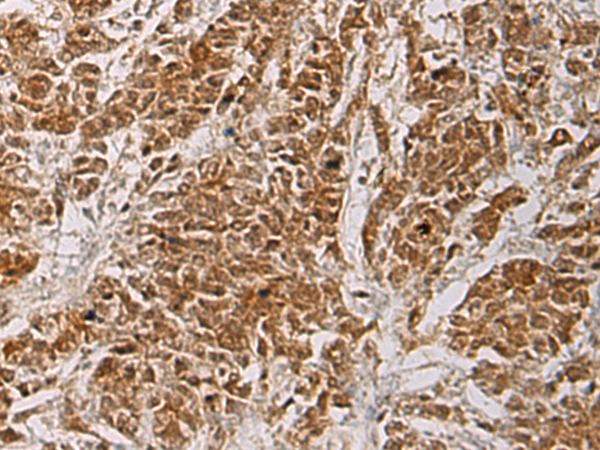

The image is immunohistochemistry of paraffin-embedded Human colorectal cancer tissue using (HOXC5 Antibody) at dilution 1/55.

IHC dilution:1:50-1:200